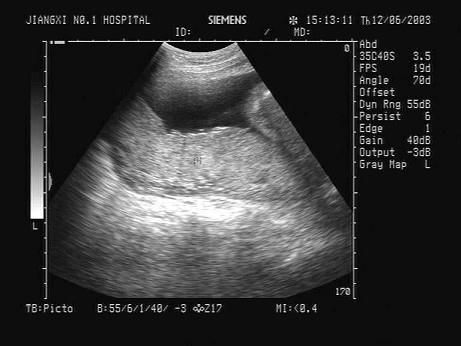

问题 根据超声声像图,提示结构为?(?)

选项 A.脐带 B.胎盘 C.胎儿躯干 D.胎儿臀部 E.子宫肌层

答案 B